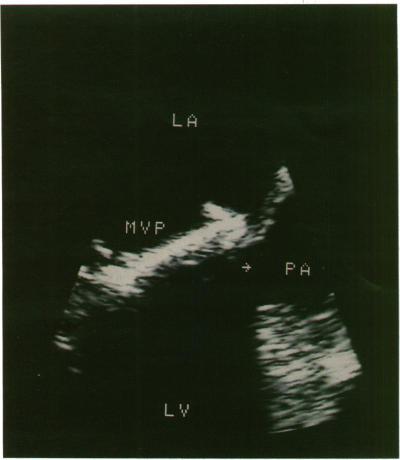

To determine whether biplane transoesophageal imaging offers advantages in the evaluation of mitral prostheses when compared with standard single transverse plane imaging or the precordial approach in suspected prosthetic dysfunction.

Transverse plane transoesophageal imaging alone identified all 31 medial/lateral paravalvar leaks but only 24/30 of the anterior/posterior leaks. Combining the information from both imaging planes confirmed that biplane scanning identified all paravalvar leaks. Five of the six patients with prosthetic valve endocarditis, all three with valvar thrombus or obstruction, and all three with mitral annulus rupture were diagnosed from transverse plane imaging alone. Longitudinal plane imaging alone enabled diagnosis of the remaining case of prosthetic endocarditis and a further case of subvalvar pannus formation.

Transverse plane transoesophageal imaging was superior to the longitudinal imaging in identifying medial and lateral lesions around the sewing ring of a mitral valve prosthesis. Longitudinal plane imaging was superior in identifying anterior and posterior lesions. Biplane imaging is therefore an important development in the study of mitral prosthesis function.